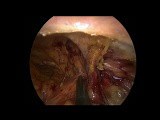

Surgery - Open Inguinal Hernia Repair

Exam - Direct Inguinal Hernia Repair

Operative Procedure - Direct Inguinal Hernia